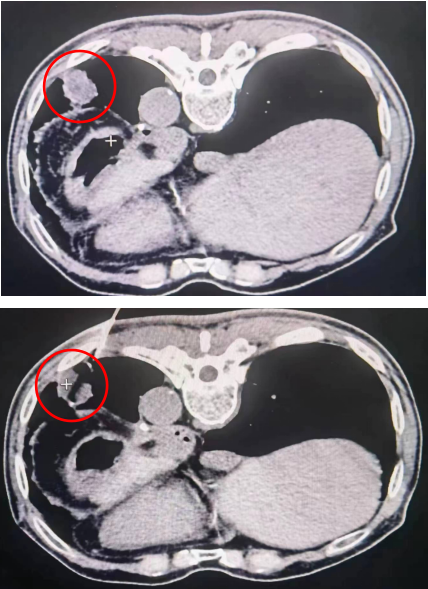

患者男性,79岁,食管恶性肿瘤手术切除后肺转移。病灶距离胸膜较近,常规微波及射频等热消融,会导致剧烈疼痛而无法完成手术,同时可能导致胸膜及神经、大血管损害,导致严重并发症甚至危及生命。经介入科会诊决定,采用最先进的氩氦刀消融治疗。术中精准定位后,采用氩氦刀治疗,手术顺利,全程患者无明显疼痛及不适,术后即可见到肿瘤组织完全坏死,手术取得圆满成功。

△肿瘤冷冻后形成“冰球”